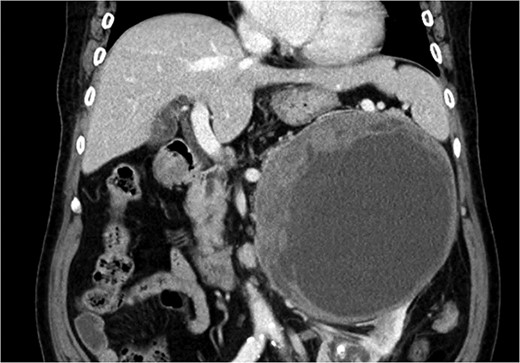

An 87-year-old female, with no past medical history, was admitted to the emergency center in our tertiary institution with a 1-month history of abdominal pain and discomfort. Initial workup using abdomino-pelvic computed tomography (APCT) presented a 16-cm-sized heterogeneous tumor in the left adrenal gland (Fig. 1). She was referred to the endocrine department for further evaluation. The results of laboratory tests, including those for measuring plasma levels of adrenocorticotrophic hormone, cortisol, aldosterone, epinephrine, norepinephrine, metanephrine, dehydroepiandrosterone sulfate as well as urine levels of epinephrine, norepinephrine, metanephrine, vanillylmandelic acid and homovanillic acid were within normal limits. Plasma renin activity was also normal. The levels of serum markers for carcinoma were within normal limits radiolabeled metaiodobenzylguanidine single photon emission computed tomography (I-123 MIBG SPECT) presented a huge mass with mild peripheral uptake of the left adrenal gland (Fig. 2). Finally, positron emission tomography (PET) was done for evaluation of distant metastasis. PET showed the accumulation of fluorodeoxyglucose (FDG) in the left adrenal tumor with [maximum standardized uptake value (SUVmax: 7.4)] and lymph nodes in the para-aortic area (SUVmax: 2.4; Fig. 3). We initially expected adrenocortical carcinoma with lymph nodes metastasis.

APCT showed a 16-cm-sized heterogeneous tumor in the left adrenal gland.